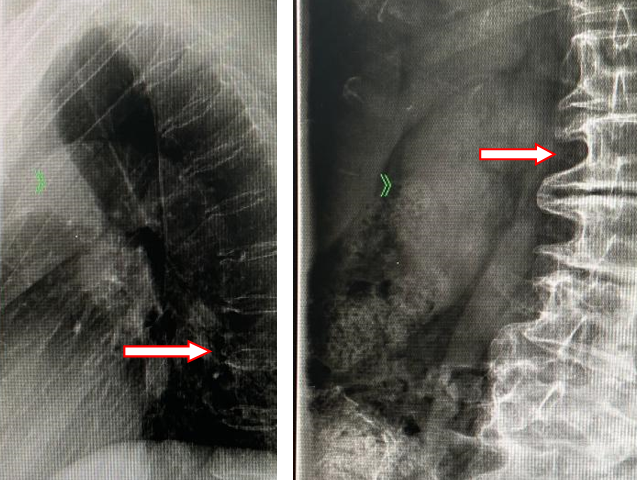

红色箭头处,为术前腰椎侧弯畸形及胸椎后凸畸形

许阿姨的腰从10年前开始就有点痛,但一直拖着没看医生。直到今年7月,她的脊柱侧弯畸形明显加重了,走500米左右就得坐下休息,腰和腿都很痛,整夜睡不着。

最开始的时候,许阿姨吃过止痛药,做过理疗,但是都没啥效果。因为情况越来越严重,家人赶紧送她去当地医院就诊,腰椎磁共振检查发现,她的第1至第5腰椎间盘突出,多处椎管狭窄,第4、第5椎体不稳、椎间盘脱出,马尾神经明显受压。